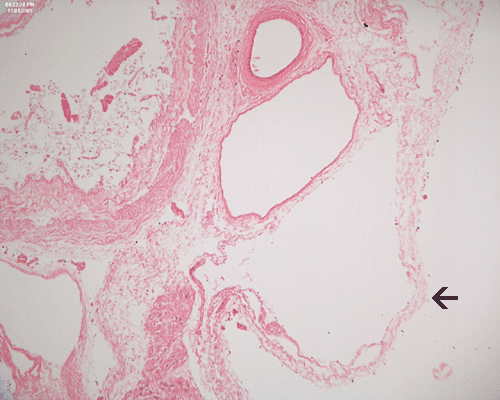

Discussion of the pathology is limited to the alimentary canal. On autopsy, the intestinal loops are largely dilated with gas accumulation. On closer examination, many small, subserosal bubbles can be seen (arrows in Panel A). The intestinal wall is also thinned out as a result of the dilatation by gas (Panel B). In the less affected areas, the intestinal  wall is not thinned out and the mucosa can still be recognized as largely intact (with autolytic changes) (Panel C and E). In the thinned out areas, the mucosa appear pink and necrotic (Panel D, F and G). The subserosal bubbles appear to be empty vesicles filled with air and they are found most frequently in the most necrotic region. In general, these features indicate widespread infarction with gas production (Panel H and I).

Pneumatosis intestinalis, usually limited to the submucosa, is seen in 50% of surgical specimens with NEC.  The gas bubbles have been shown to contain hydrogen, a product of bacterial fermentation.  More than 50% of patients who undergo laparotomy show focal reparative epithelial changes and other evidence of healing, such as the formation of granulation tissue and crypt distortion.  Villous atrophy may also be observed.  Such reparative changes suggest that NEC evolves gradually before a catastrophic event, such as perforation, brings it to clinical attention.